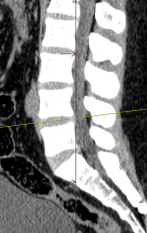

Nghiêng kỹ thuật số ±50° giúp quy trình nhanh hơn.

Chỉ với 1 click tự động xác định chính xác phạm vi quét theo giao thức đã chọn, giảm thiểu điều chỉnh thủ công phức tạp

Chỉ với 1 click định vị chính xác iso-center, tối ưu hình ảnh và liều tia, giảm thiểu phơi nhiễm